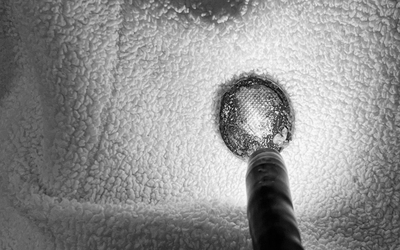

Bé 11 tháng tuổi nôn nhiều, quấy khóc dữ dội, bác sĩ phát hiện "bí mật đáng sợ"

Bệnh nhi 11 tháng tuổi nhập viện trong tình trạng nôn nhiều, quấy khóc dữ dội. Qua thăm khám và chụp X-quang, các bác sĩ phát hiện dị vật kim loại hình tròn mắc kẹt tại thực quản.